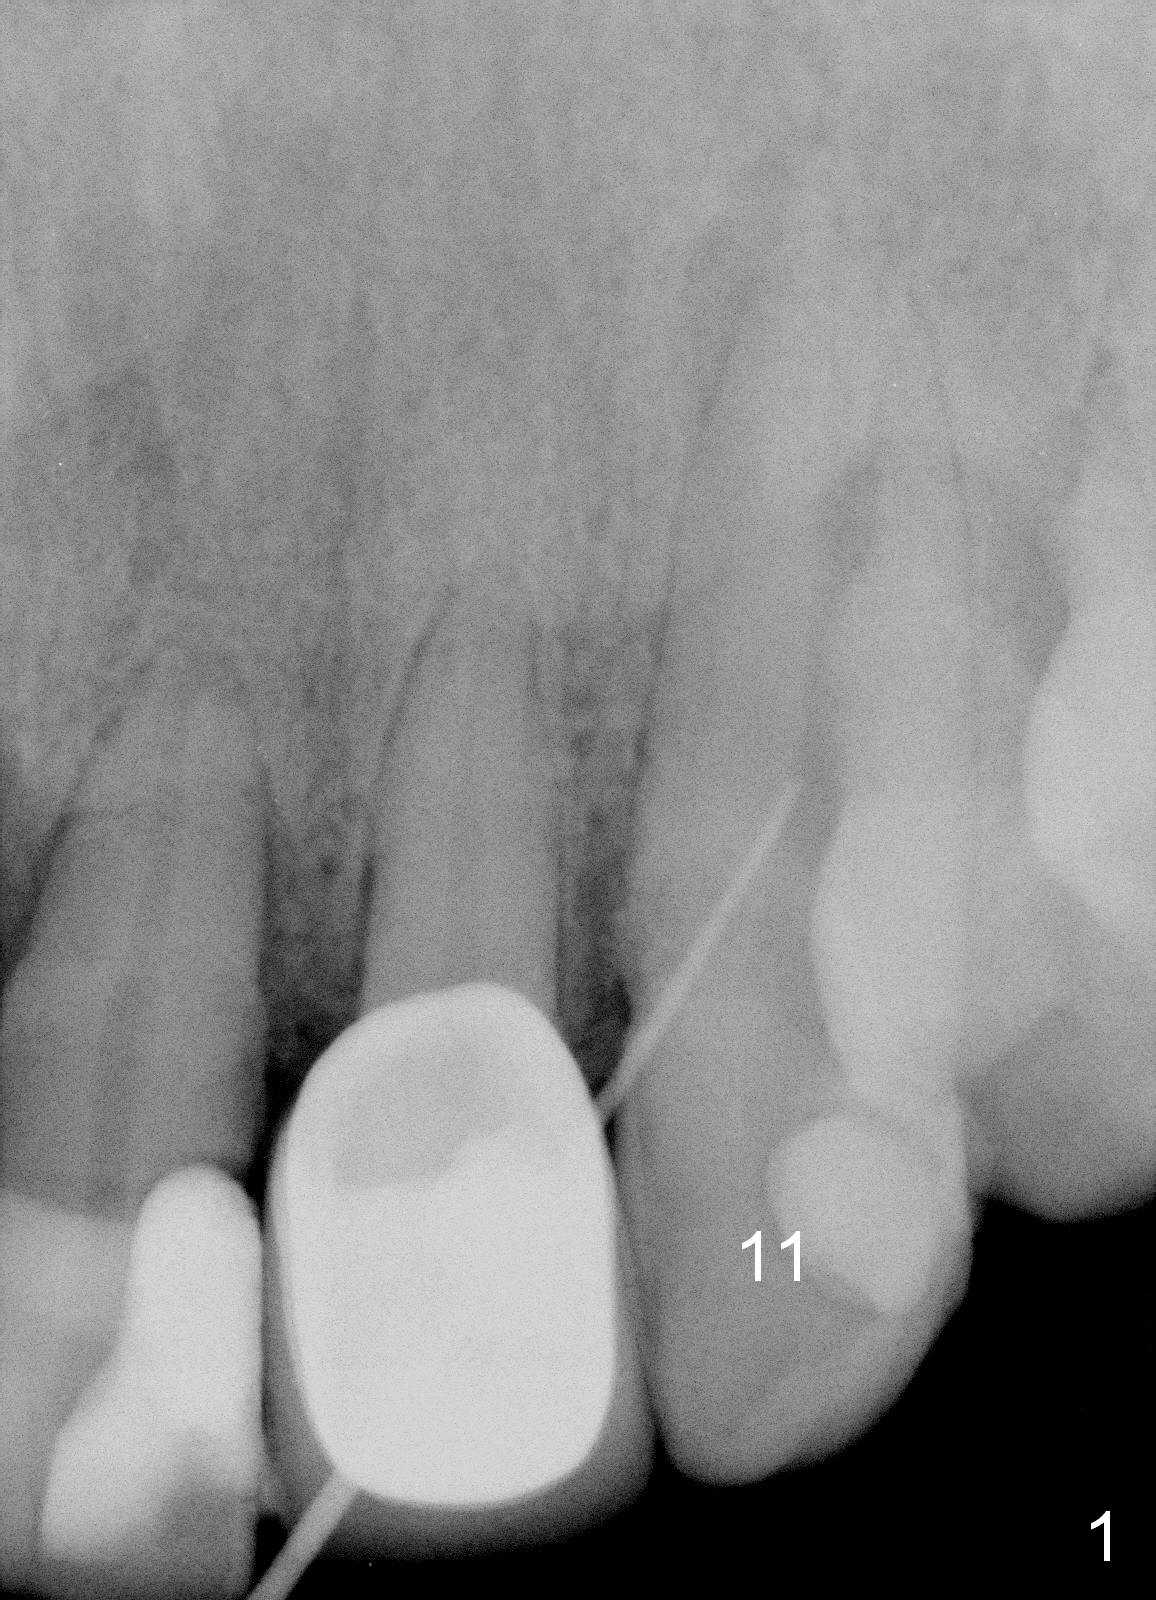

A 57-year-old man has multiple restoration. There was a fistula mesiobuccal to #11 a year ago (Fig.1,2). There is acute apical infection lately. The pulp is non-vital. Apex locator is sensitive. Two PAs are taken with #15 file at 29 mm and 33 mm (Fig.3,4). The canal is debrided until #40 hand file. The master cone with length of 28 mm is inserted below the landmark (Fig.5). Panoramic X-ray is taken for final confirmation (Fig.6).